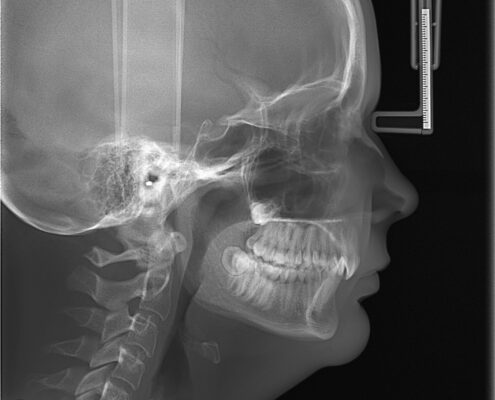

CEPH X-Ray

A cephalometric x-ray is a unique tool, which enables the dentist to capture a complete radiographic image of the side of the face. X-rays, in general, offer the dentist a way to view the teeth, jawbone and soft tissues beyond what can be seen with the naked eye. Cephalometric X-rays are extraoral, meaning that no plates or film are inserted into the mouth. Cephalometric and panoramic X-rays display the nasal and sinus passages, which are missed by intraoral bitewing X-rays.

- Provide views of the side profile of the face.

- Provide views of the jaw in relation to the cheekbone.

Cephalometric X-rays are completely painless. The head is placed between the mechanical rotating arm and the film holder, which is placed on another arm. The arm rotates around the head capturing images of the face, mouth and teeth. The clarity and sharpness of these images will depend on the positioning of the body. The images are usually magnified up to 30%, so any signs of decay, disease or injury can be seen and treated.

After capturing cephalometric X-rays, the dentist will be able to see a complete side profile of the head. This can assist in orthodontic planning, and allow an immediate evaluation of how braces might impact the facial profile and teeth. Another common use for this type of X-ray is to determine specific measurements prior to the creation and placement of dental implants.